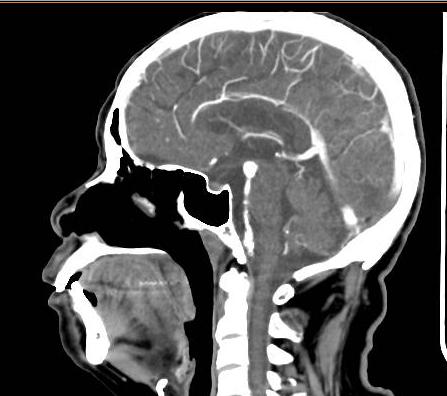

头部CTA成像

70多岁老人因“皮肤瘙痒皮疹4天伴发热2天”入急诊内科住院,经过头部CTA检查发现基底动脉末端动脉瘤,如下图